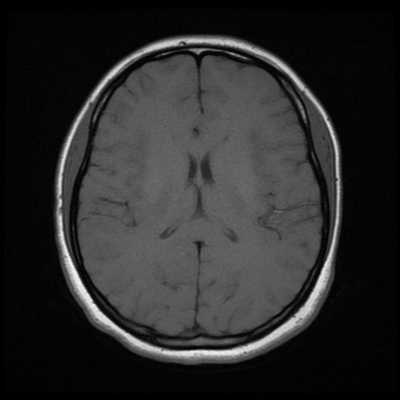

Классический пример МРТ снимков головного мозга показан на рисунках ниже. Магнитно-резонансная томография выполняется в поперечной (или аксиальной - рисунок снизу) и продольной (или сагиттальной — рисунок сверху) плоскостях.

Исследование выполняется в нескольких режимах. Основные из них Т1 и Т2. Изображения, полученные в данных режимах, часто также называют Т1-взвешенными или Т2-взвешенными снимками. Изображения, показанные выше, сделаны в Т1-режиме.

Главное отличие этих режимов - в том, как на снимках отображается жидкость и воздух. В Т1 режиме ткани, содержащие большое количество воды, имеют более темную окраску, в то время как в Т2 режиме они яркие, светлые. Это легко понять, посмотрев на снимки выше - глазные яблоки визуализируются в виде светлых парных округлых образований с одной стороны яркие и светлые, с другой - темные. Следовательно, снимок справа сделан в Т1 режиме, снимок слева - в Т2. Также существует разница в том, как в этих режимах отображается серое вещество головного мозга. В Т2 режиме оно светлее, чем белое вещество.

Как же узнать, есть ли на снимках признаки болезни? Самое главное - запомнить, как выглядит головной мозг здорового человека. Врач, изучая снимки пациентов, постоянно сравнивает их с нормальными снимками, хранящимися у него в голове. Чтобы понять, как это происходит - посмотрите на снимки внизу: